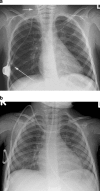

Central venous access is increasingly becoming the domain of the radiologist, both in terms of the insertion of central venous catheters (CVCs) and in the subsequent management of these lines. This article seeks to provide an overview of the CVC types available for paediatric patients and a more detailed explanation of the spectrum of complications that may lead to catheter malfunction. A standard catheter contrast study or 'linogram' technique is described. The normal appearances of such a study and a detailed pictorial review of abnormal catheter studies are provided, together with a brief overview of how information from catheter investigations can guide the management of catheter complications.